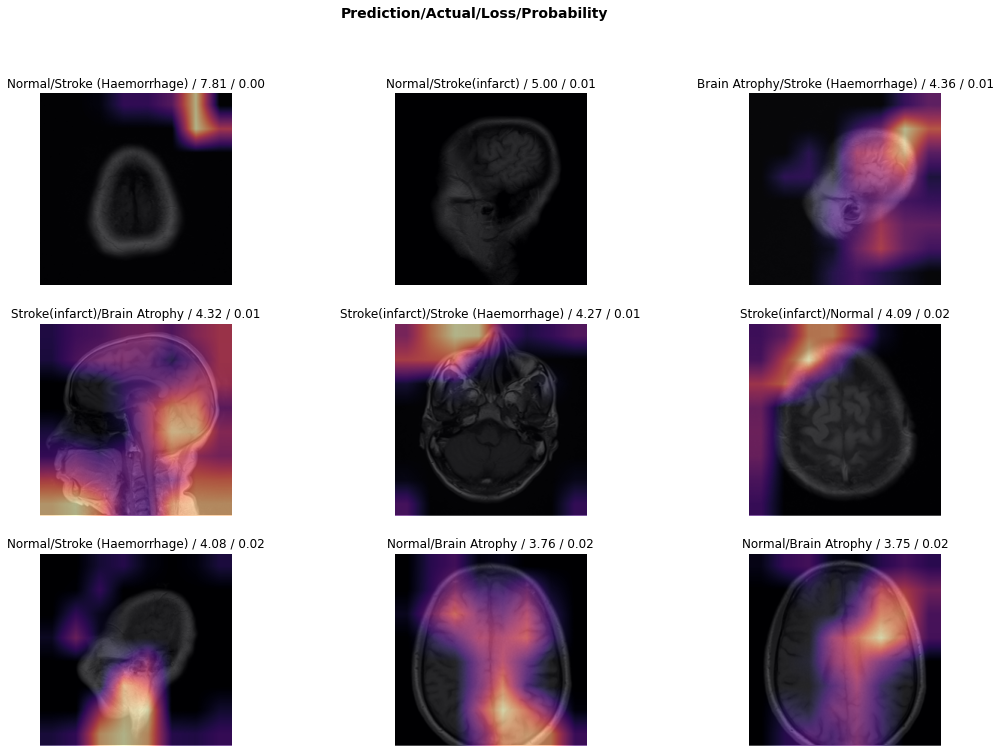

5.2 Experiment II: Harvard Whole Brain Atlas Dataset

5.2.1 Stage I: Retraining the Network

Following the same methodology used in experiment 5.1 stage 5.1.1, we froze the convolution layers of the network and did not update it during this stage. The learning rate hyperparameter was assigned 1e31superscript𝑒31e^{-3} and the number of epochs was set to 6. The epoch set to 6 to avoid overfitting the model on the training set. At this first stage, the training model achieved an overall accuracy of 92.47% in a fivefold cross-validation strategy. Fig 15 shows the top miss-classified images during this phase of training.

Refer to caption

Figure 15: Illustration of top miss-classified images after stage I of training